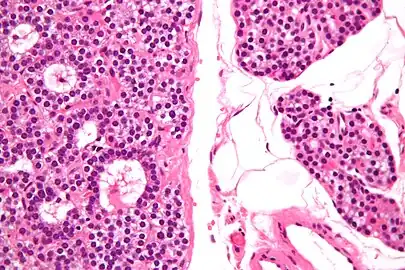

Micrograph of a parathyroid adenoma (left) and normal parathyroid gland (right). H&E stain.

Normal parathyroid gland with prominent adipose tissue is seen on the right of the image.-High magnification